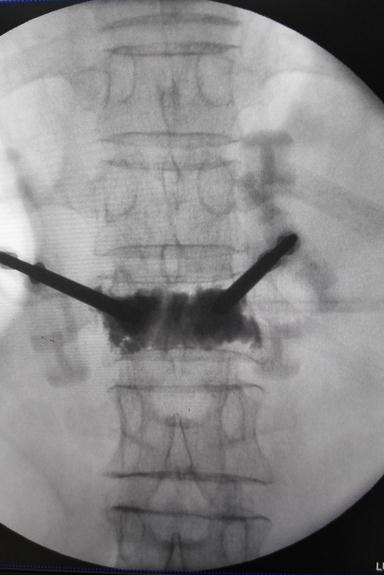

3.已开展胸腰椎手术:胸腰椎压缩性骨折经皮椎体成形术(PVP、PKP)、经皮椎弓根螺钉内固定术、经Wiltse入路骨折复位钉棒系统内固定术、胸椎后凸畸形矫形术。后路腰椎椎间融合术(PLIF、TLIF、MIS-TLIF、OLIF)、腰椎滑脱(单节段、多节段)后路减压固定融合术、腰椎间盘突出可视化椎间孔镜髓核摘除术、显微镜下减压髓核摘除术、显微镜下骶管囊肿切除术、腰椎结核一期椎间孔镜下病灶清除引流术二期显微镜下病灶清除减压经皮椎弓根螺钉固定术、老年胸腰椎骨折PVP+骨水泥加强钉固定术、脊柱术后翻修、脊柱肿瘤手术治疗。

2.椎间孔镜技术:目前国际脊柱微创外科领域公认的成熟技术。我院引进国际先进的新一代Maxmore椎间孔镜,具有更安全、更精准、更有效的治疗腰椎间盘突出症。具有微创:不开刀,切口仅7mm,只缝一针;安全性高:局部麻醉,可视化,出血少,术中能与病人沟通;并发症少:创伤小,很少形成血肿,感染可能性小,不损伤脊柱的稳定性;康复快:术后次日可下床活动,循序渐进开始康复功能锻炼;满意度高:立即缓解疼痛;费用低:较开刀费用节省约50%。